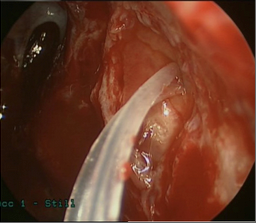

Dacryocystorhinostomy (DCR) surgically bypasses the nasolacrimal duct and thus is the primary surgery for NLDO. It requires a patent punctum and canaliculus. A fistula is created from the lacrimal sac to the lateral nasal mucosa and a silicone tube is temporarily placed through this fistula to maintain patency. See the EyeWiki article a “Dacryocystorhinostomy” for more details about DCR.

DCR can be approached endoscopically (endonasal, or “endoDCR”) or via an external incision. External DCR is currently the gold standard of lacrimal bypass surgery, and multiple studies show a success rate over 95% for NLDO. Historically, external DCR has had greater success rates to endoscopic DCR. However, more recent studies suggest the success rate of endoDCR is approaching that of external DCR.[1] There is a high learning curve for endoscopic DCR, and this certainly influenced prior studies. Advantages of endoscopic DCR are that it is less invasive, has a shorter operative time, preserves lacrimal pump function, has faster recover, and avoids an external scar. However, the initial cost of endoscopic DCR can be high, including equipment price and the time spent learning the procedure. Endoscopic DCR assisted with laser ostium creation has been shown to have a lower success rate than endoDCR (71% and 83%, respectively in a study comparing the two), but has less bleeding and a quicker recovery time. Some authors suggest endoscopic DCR for the treatment of SANDO, as intranasal abnormalities can be directly visualized during surgery and additional nasal surgery can be accomplished if needed, generally with the assistance of an experienced rhinologist.

Patients should avoid exercise and strenuous activity for one week after DCR. Patients are advised to avoid blowing their noses during this week. Patients should return for follow-up one month and 2-3 months after the surgery. The silicone tubes placed during DCR are usually removed in the office 4-8 weeks after the surgery, depending on the degree of inflammation. In certain cases of SANDO with a propensity for robust postoperative inflammation, some authors advocate for endonasal debridement in the office 2-6 weeks after the surgery.